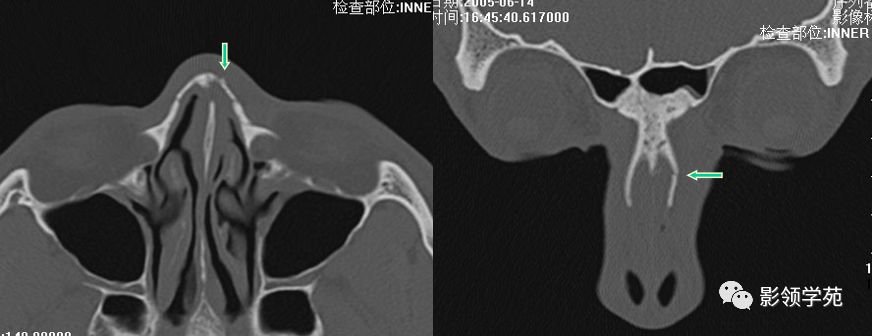

鼻骨横断面HRCT

鼻骨冠状面HRCT

右侧鼻骨线形骨折

鼻骨线形骨折

左侧鼻骨线形骨折